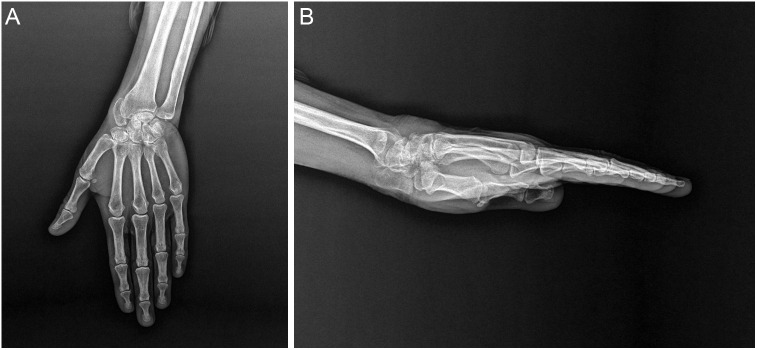

孤立性舟状骨脱位是一种极为罕见的损伤。如果不及时治疗,后果可能是灾难性的。本文报道一例被忽视的开放性舟状骨脱位损伤的晚期并发症。一名63岁妇女因左腕疼痛和活动受限的症状入院骨科门诊。她的病史显示,大约45年前,由于被困在一辆手推车和一棵树之间,她的左手腕曾有过开放性损伤。x线和计算机断层显示舟状骨掌侧脱位、月骨塌陷、晚期关节炎改变和月头关节囊性改变。决定手术治疗。左腕行舟状骨切除及放射性腕关节融合术。孤立性舟骨脱位是一种罕见的损伤。在急性期早期识别和治疗可预防严重并发症并取得成功。晚期手腕关节炎可在延迟病例中观察到。对于完全丧失运动能力的晚期病例,放射性腕关节融合术是一个成功的治疗选择。

Isolated dislocation of the scaphoid bone is an extremely rare injury. If left untreated, results may be catastrophic. This paper presents a late complication of a neglected open scaphoid dislocation injury. A 63-year-old woman was admitted to the orthopedic outpatient department with symptoms of pain and restricted movement in her left wrist. Her medical history revealed a previous open injury to her left wrist approximately 45 years ago due to being trapped between a cart and a tree. X-ray and computed tomography showed volar dislocation of the scaphoid bone, collapse of the lunate bone, advanced arthritic changes, and cystic alterations in the lunocapitate joint. The decision on surgical treatment was made. Scaphoid excision and radiometacarpal fusion surgery were performed on her left wrist. Isolated scaphoid dislocations are rare injuries. Early recognition and treatment in the acute phase prevent severe complications and yield successful results. Advanced wrist arthritis can be observed in delayed cases. Radiometacarpal fusion is a successful treatment option for advanced cases with complete loss of motion.